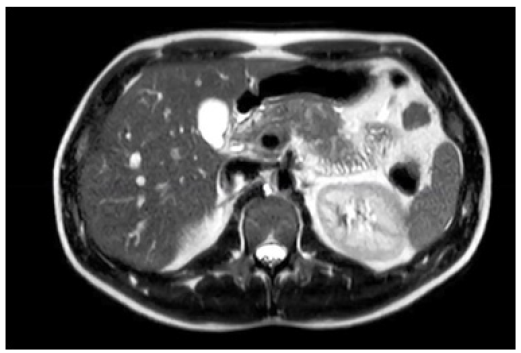

On the second day of hospitalization and the fifth day of illness, due to persistent abdominal pain without improvement, accompanied by a fever spike of 38.4°C and the presence of an epigastric mass on physical examination, a contrast-enhanced CT scan was ordered due to suspicion of local complications. Blood tests were repeated, including procalcitonin levels and blood cultures. In the meantime, the patient received only symptomatic treatment without antibiotics. Laboratory results returned with Hb 13.2g/dL, Hct 39%, WBC 17,270/mm³ with 82% segmented neutrophils, platelets 192,000/mm³. Creatinine was 0.7mg/dL, electrolytes were within normal limits. Liver function tests showed GOT 22U/L, GPT 11U/L, total bilirubin 0.77mg/dL with direct bilirubin 0.33mg/dL, amylase 509U/L, and lipase 312U/L. Procalcitonin was 0.3ng/mL, and no bacterial growth was observed in the blood culture. The contrast-enhanced abdominal and pelvic CT scan revealed a normal liver and gallbladder with no tomographically evident alterations. The pancreas was globally enlarged, with the head measuring 48mm in its craniocaudal diameter, and the margins were diffuse with peripancreatic fat stranding and adjacent fluid collections extending along the left paracolic gutter down to the pelvic cul-de-sac. There was homogeneous enhancement in the head and body of the pancreas, with decreased enhancement noted in the tail, suggesting a possible necrotic area involving less than 30% of the parenchyma. The main pancreatic duct was preserved caliber. These findings were consistent with acute pancreatitis with peripancreatic fluid collections, a tomographic severity index of 5 points, classified as moderate pancreatitis (Balthazar D), with probable necrosis involving less than 30% of the pancreas (Figure 2).

Figure 2: Contrast-Enhanced CT Abdomen. Peripancreatic fluid collections. Balthazar D, probable necrosis less than 30%.